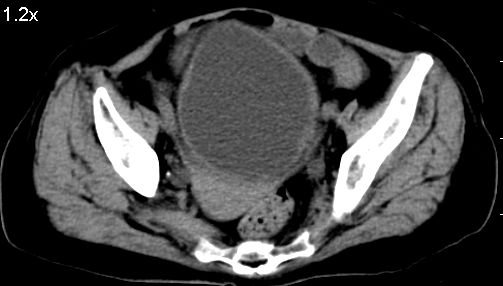

标题: CT10133:F、74岁,反复血尿10天。 [打印本页]

标题: CT10133:F、74岁,反复血尿10天。

考虑膀胱癌可能性大伴双侧输尿管下端扩张.

1.膀胱后壁见不规则致密影,占位?膀胱内凝血块?建议俯卧位扫描、膀胱镜检查.

2.双侧输尿管下段扩张.

膀胱三角区不规整软组织改变,双侧输尿管扩张,所以占位性病变肯定首先考虑,建议改变体位扫描除外游离血块影,但老年人出血原因一定要查明。

1.膀胱后壁见不规则致密影,随体位改变,为膀胱内凝血块;

2.双侧输尿管下段扩张.输屎管结石可能大。建议作进一步检查。

2.双侧输尿管下段扩张.输屎管结石可能大。

2.双侧输尿管下段扩张,临床有血尿病史,建议进一步检查,找出血原因。